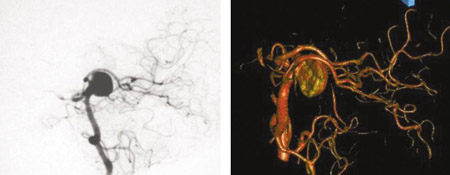

Comparison of 2-dimensional catheter angiography (left) with 3-dimensional catheter angiography (right) showing a basilar tip aneurysm

From: Sellar M. Practical Neurology. 2005;5:28-37. Used with permission